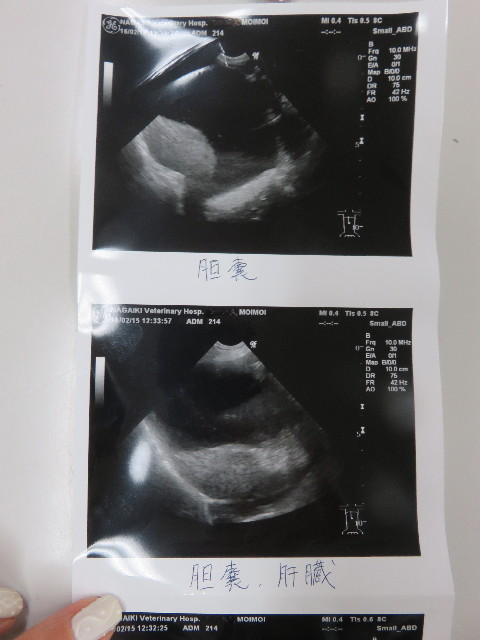

●エコー

○脾臓のマス、20.7×11.9cmと前回(前回12.7は17.5×12.2)

よりけっこう大きくなってしまっていました。

(前回はその前より小さくなっていた)

先生的には悪いものにはみえないので、これで脾臓をとる必要

があるとは思えない。とのこと。

他の検査としては鎮静剤をかけて針検という方法もありますが、

針が届くかどうかわからないそうです。

とにかく、次回のエコーは1ケ月後にして経過観察をします。